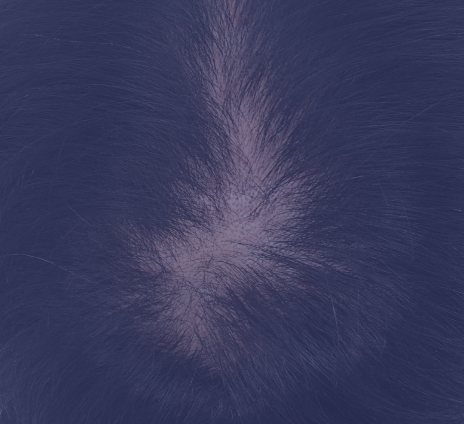

여성형 탈모

가르마와 함께 정수리 옆머리와 뒷머리의 모발이 얇아지는 여성의 탈모

정수리/가르마 확산성 탈모